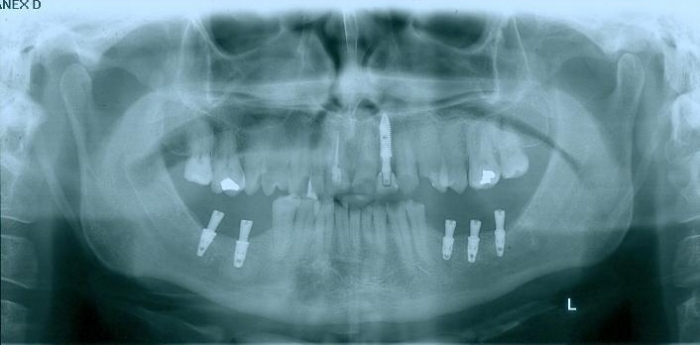

Raio - x inicial em 2014